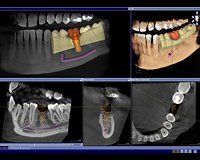

Die 3D-Diagnostik (Digitale Volumentomografie) ist die modernste und präziseste Röntgenmethode. Mit Hilfe der dreidimensionalen Darstellung der Kieferregion kann der optimale Implantationsort millimetergenau festgelegt werden.

Die digitale Volumentomografie bietet nicht nur eine optimale und präzise Planung für Zahnimplantate, sondern ist darüber hinaus einzigartig in der diagnostischen Unterstützung bei allen größeren zahnärztlichen Eingriffen.

Mit seiner hohen Aufnahmequalität lassen sich auch feinste Strukturen in Knochen und Gewebe erkennen...

...und Implantate punktgenau und vorausschauend planen.

Egal ob in der Panorama-Aufnahme oder in einem dreidimensionalen Volumen, mit unserem neuen DVT sehen wir mehr und sparen Zeit bei der Befundung.